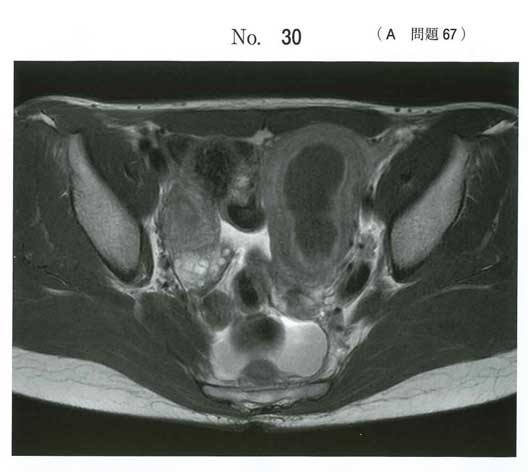

腎無形成+重複子宮による月経困難症でしょうか。

a. OHVIRA症候群?

OHVIRA症候群(またはWunderlich症候群)ですね

腎無形成だから子宮にも奇形ありそう?って考えれば…!

知らなくても腎無形成から発生系疾患と推察させる問題